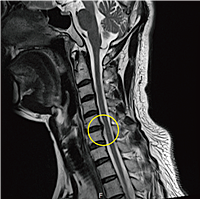

목디스크에 좋은 운동 10가지 동영상을 찾고 계신가요? 목디스크는 현대인에게 매우 흔한 문제로, 잘못된 자세와 생활 습관에서 비롯될 수 있습니다. 목디스크로 인한 통증을 줄이고, 목과 어깨 근육을 강화하기 위해서는 꾸준한 운동이 필요합니다. 이 글에서는 목디스크를 완화하고 예방하는 데 도움이 되는 10가지 운동과 함께, 각 운동에 대한 동영상을 소개합니다. 운동을 통해 목 건강을 지키고, 통증 없는 삶을 유지하는 방법을 알아보세요.

목디스크에 좋은 운동 10가지 동영상을 통해 목디스크를 예방하고 완화하는 방법을 알아보았습니다. 목디스크는 올바른 운동과 생활 습관 개선을 통해 충분히 예방하고 관리할 수 있는 질환입니다. 목과 어깨 근육을 강화하고, 스트레칭을 통해 유연성을 높이는 것이 중요합니다. 이 글에서 소개한 운동들을 동영상과 함께 참고하여 꾸준히 실천해보세요. 건강한 목을 유지하는 데 큰 도움이 될 것입니다.